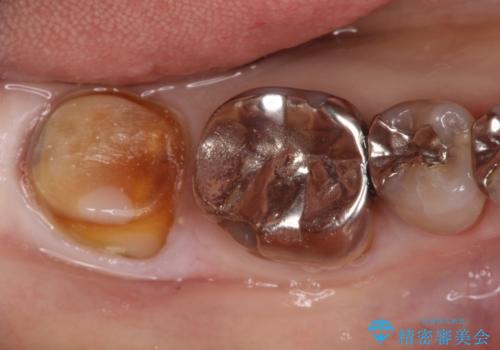

- 他院で入れたセラミックインレーがかけたことを主訴に来院されました。

他の部位にもむし歯を認めたため、優先度の高い歯から治療を行っております。

咬合力が強くかかる部分には欠けるリスクのほとんどない金属を用いることが最良ですが審美性に劣ります。

今回は白い材料での修復を希望されたため、欠けるリスクが高いセラミックインレーは避け、セラミッククラウンにて治療を行いました。